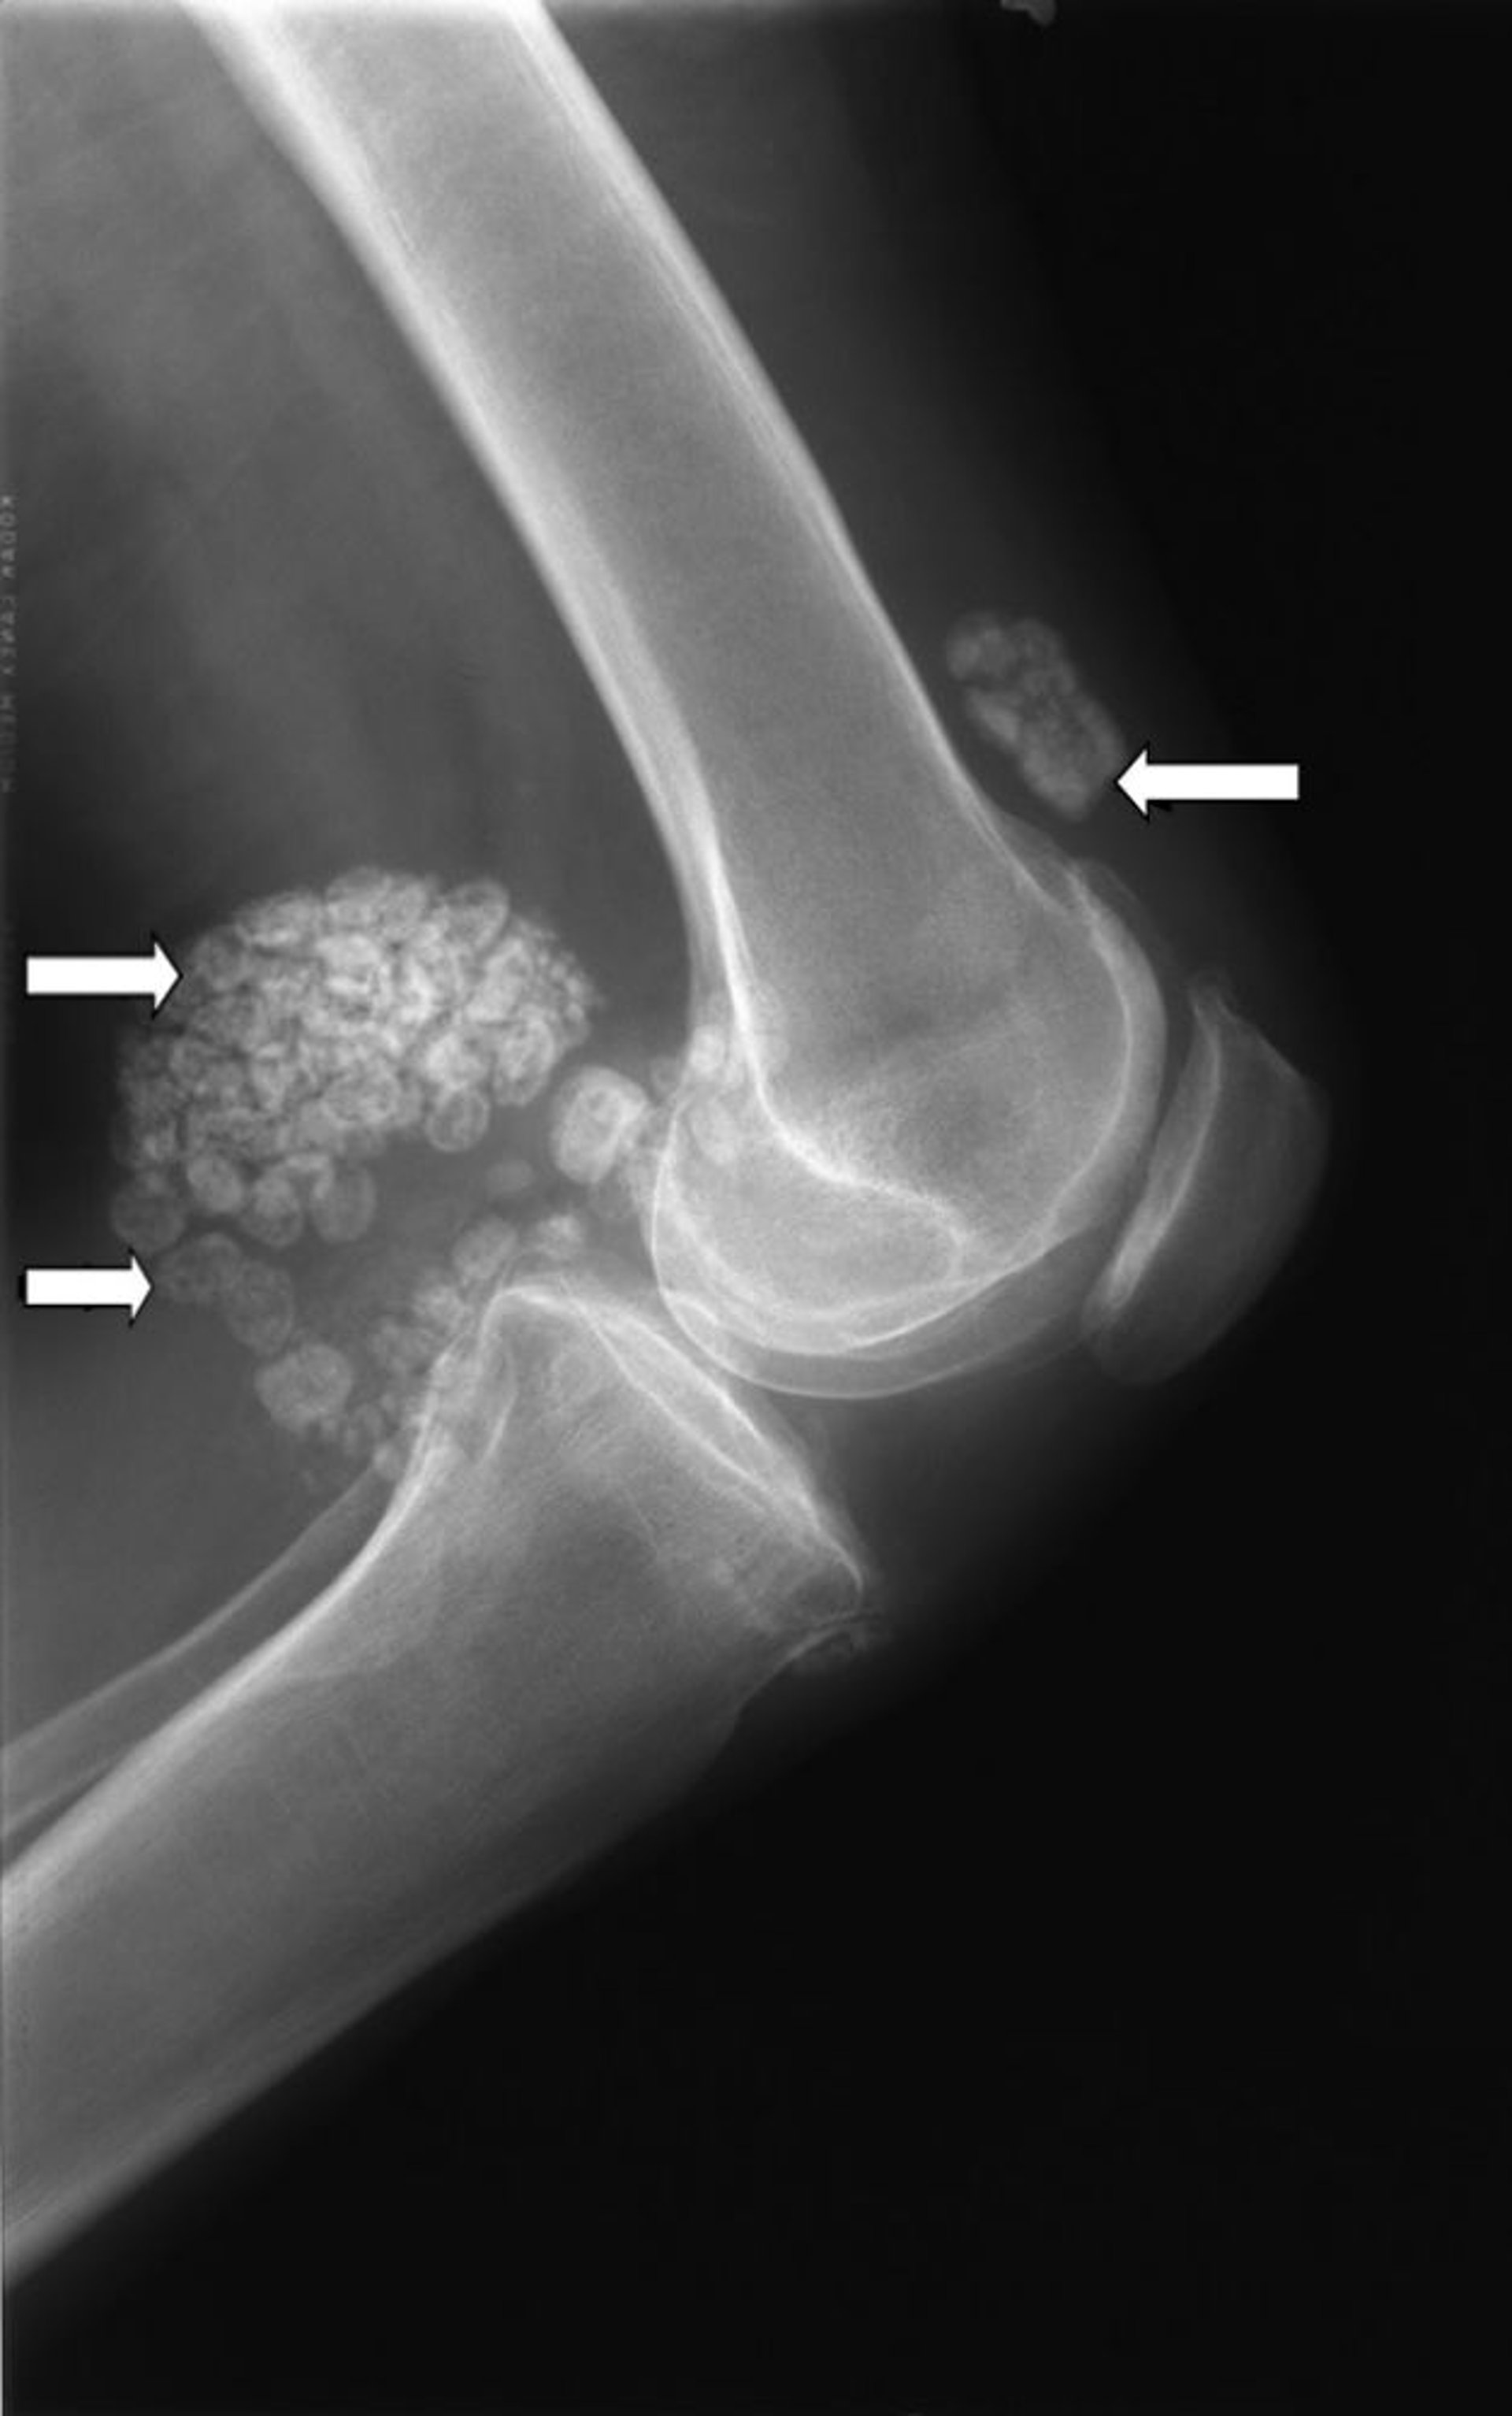

윤활막 연골종증

이 무릎 X-레이는 윤활막 연골종증으로 알려진 여러 개의 연골 응괴(화살표)를 보여줍니다.

이미지 제공: Michael J. Joyce, MD 및 Hakan Ilaslan, MD.